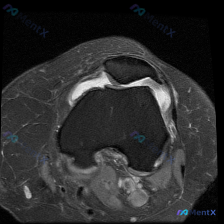

今天看到一个很有代表性的读片问题,整理出来和大家分享讨论:问题是判断这张髌股关节轴位T1加权MRI上有没有软骨异常,我们一步步梳理思路。 一、先看影像基本信息 这是一张膝关节MRI的轴位T1加权图像,扫描层面位于膝关节上方的髌股关节层面: 1. 骨骼结构:髌骨位于前方,骨皮质边缘清晰,骨髓脂肪信号正...

最近碰到一个有意思的读片病例,临床怀疑膝关节软骨异常,给了一张髌股关节轴位T1加权MRI,整理了一下分析思路分享给大家。 一、病例基本影像信息 这是单张膝关节髌股关节水平的轴位T1加权MRI扫描图: 1. 扫描层面:髌股关节水平,可见上方髌骨、下方股骨滑车沟的关节结构 2. 骨骼:股骨远端骨皮质完整...

看到这个挺有代表性的病例,整理出来和大家分享一下思路。 病例基础信息 问题是:患者有膝前痛症状,临床怀疑软骨异常,提供了一张膝盖MRI-T1加权轴位图像,问图像里能看到什么病变。 影像读片结果 我们先看这张图像本身: 1. 扫描层面:膝关节上方,显示髌骨和股骨远端髌股关节面 2. 骨质结构:股骨远端...

看到一份针对单张膝关节MRI的软骨异常评估咨询,整理了完整的分析思路分享给大家。 病例/影像基础信息 问题核心:用户提供单张膝关节轴位T1加权MRI图像,询问图像中是否存在软骨异常。 影像所见(基于提供图像): 1. 扫描层面为膝关节轴位,涵盖股骨远端滑车区与髌骨 2. 股骨髁、髌骨骨髓信号正常(T...

病例读片:膝关节软骨异常的影像陷阱 先给大家看一下这份病例的基本影像资料:这是一张膝关节MRI-T1加权序列的轴位图像,扫描层面位于股骨远端髁间窝与髌股关节层面。 影像基本信息整理 1. 骨骼结构:股骨远端骨皮质、骨髓信号正常,髌骨形态完整,骨皮质连续,骨髓信号无异常; 2. 关节软骨:髌骨后方关节...

今天分享一个很有代表性的读片病例,核心矛盾是「临床怀疑软骨异常,但单张MRI没看到明确病变」,整理了完整分析思路,大家一起讨论。 病例基础信息 这是一张膝关节MRI的T1加权轴位图像,聚焦显示髌股关节及周围软组织结构,患者主诉提示存在软骨异常相关问题。 影像基础评估结果 1. 骨骼结构:股骨远端滑车...